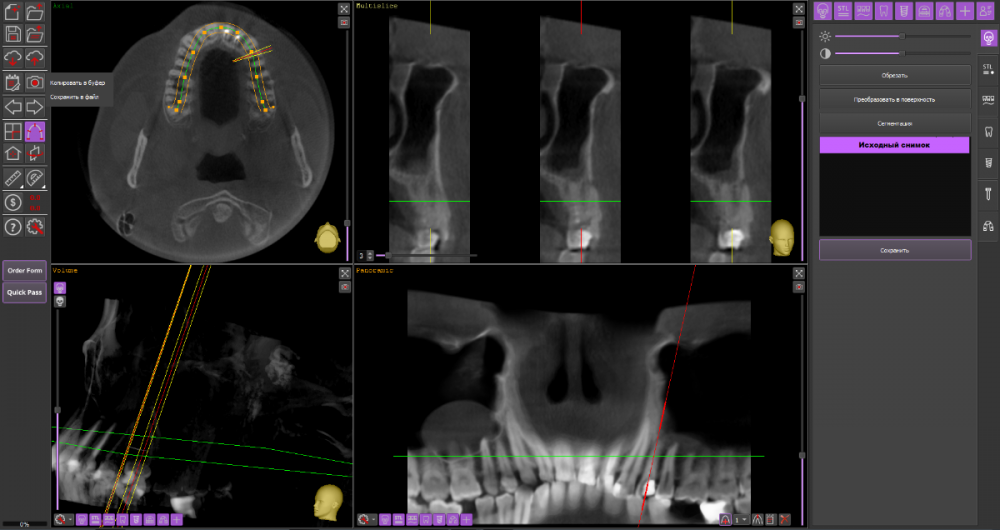

alexx123 Опубликовано 9 декабря, 2021 Поделиться Опубликовано 9 декабря, 2021 (изменено) Здравствуйте. 24-й зуб. Периодонтит осложненный периоститом. Посмотрите пожалуйста насколько реально сохранить зуб. Лечили в поликлинике глубокий кариес. Через несколько месяцев часть зуба откололась, появилось воспаление и позже на челюсти вылезла большая шишка. При этом боли не было. Зуб не шатался. Обратился в хорошую платную клинику. Абсцесс вскрыли, начали лечение эндо. Уже 4 раза чистили каналы. Положительная динамика вроде бы есть, но очень медленная. Есть ли смысл продолжать лечение или все же удалить? И еще вопрос, реально ли сделать резекцию верхушки корня? Хирург сказал, что скорее всего нет. КТ до начала лечения. https://cloud.mail.ru/public/Zfhf/NcjmRfbej Изменено 9 декабря, 2021 пользователем alexx123 Ссылка на комментарий

alexx123 Опубликовано 20 декабря, 2021 Автор Поделиться Опубликовано 20 декабря, 2021 (изменено) В другой клинике сказали, что корни вылечить можно, но коронковая часть слишком сильно разрушена. Настоятельно советуют удалить зуб и поставить имплант. Что посоветуете? Абсцесс снова вскрыли. Каналы пролечили под микроскопом (кстати ценник оказался не сильно дороже чем без микроскопа). Вроде бы пошла положительная динамика. Через неделю либо на пломбировку либо на удаление. Надо принимать решение. Изменено 20 декабря, 2021 пользователем alexx123 Ссылка на комментарий